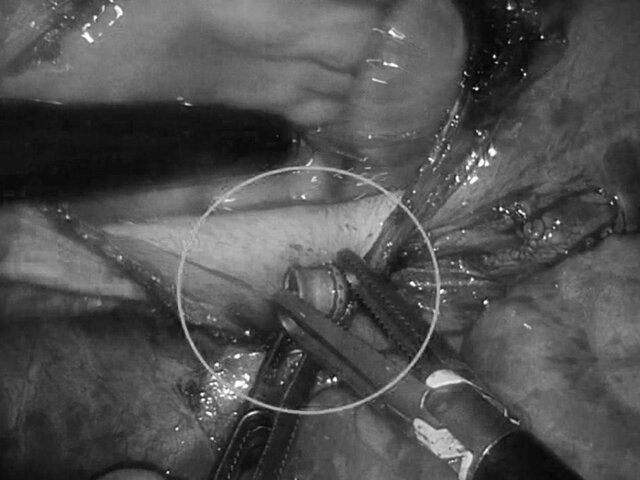

В связи с этим было принято решение провести малоинвазивную операцию. Она предполагает вскрытие перикарда и работу в миллиметрах от жизненно важных органов. В результате хирурги извлекли пулю без единого разреза, уточнил Степаненко.